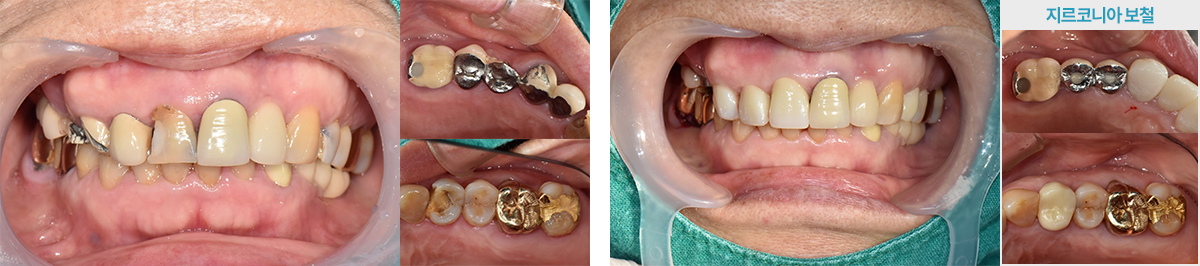

· (임플+지르) 기존 보철물 뜯어내고 임플란트 + 일부 신경치료 후 지르코니아 보철물 진행 case

치료 후 사진은

자세히보기에서 확인하실 수 있습니다.

+ 자세히보기